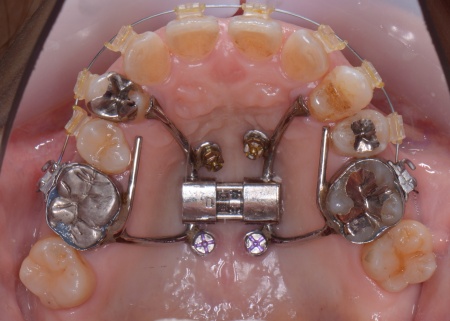

①上あごの骨が狭く歯が並ぶスペースが不足しているため、まず上あごの骨の幅を広げる急速拡大装置を装着する。

成人になってからの骨の拡大は難しいものの、あごの骨に矯正用の小さなネジを埋め、そこを固定源として効率的に歯を動かす治療を併用することでスムーズに拡大を進める。

②①と並行して上下歯列にワイヤー矯正のマルチブラケット装置を装着し、歯並びと噛み合わせを整える。